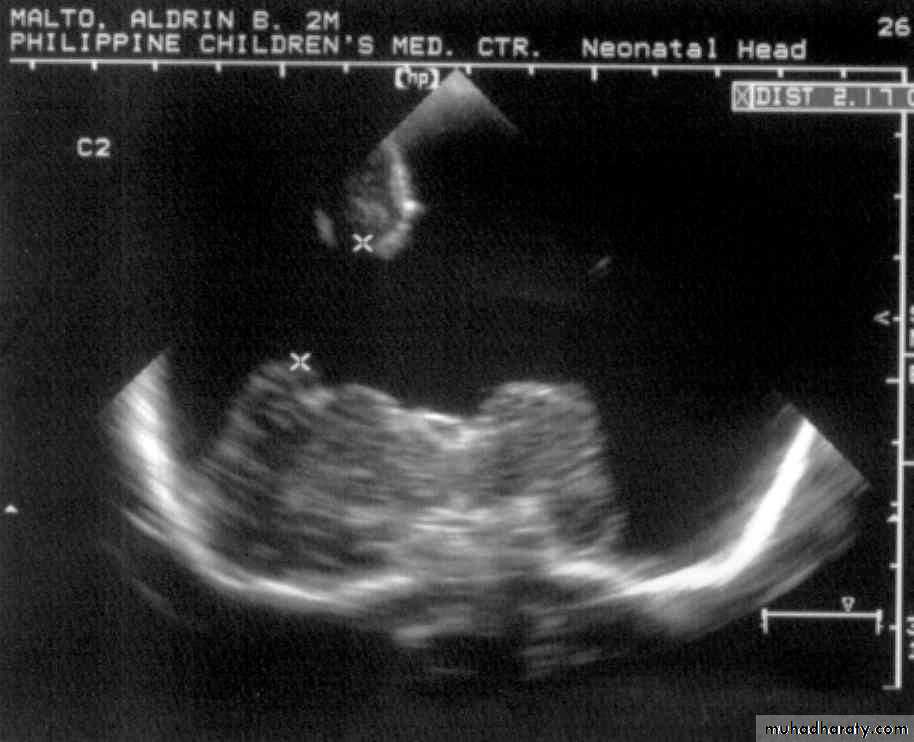

A.M., 2 months old

was noted to be microcephalic w/ szPorencephalic Cyst

SchizencephalyAbsent Septum Pellucidum

Dysgenetic Corpus Callosum

Aqueductal Stenosis